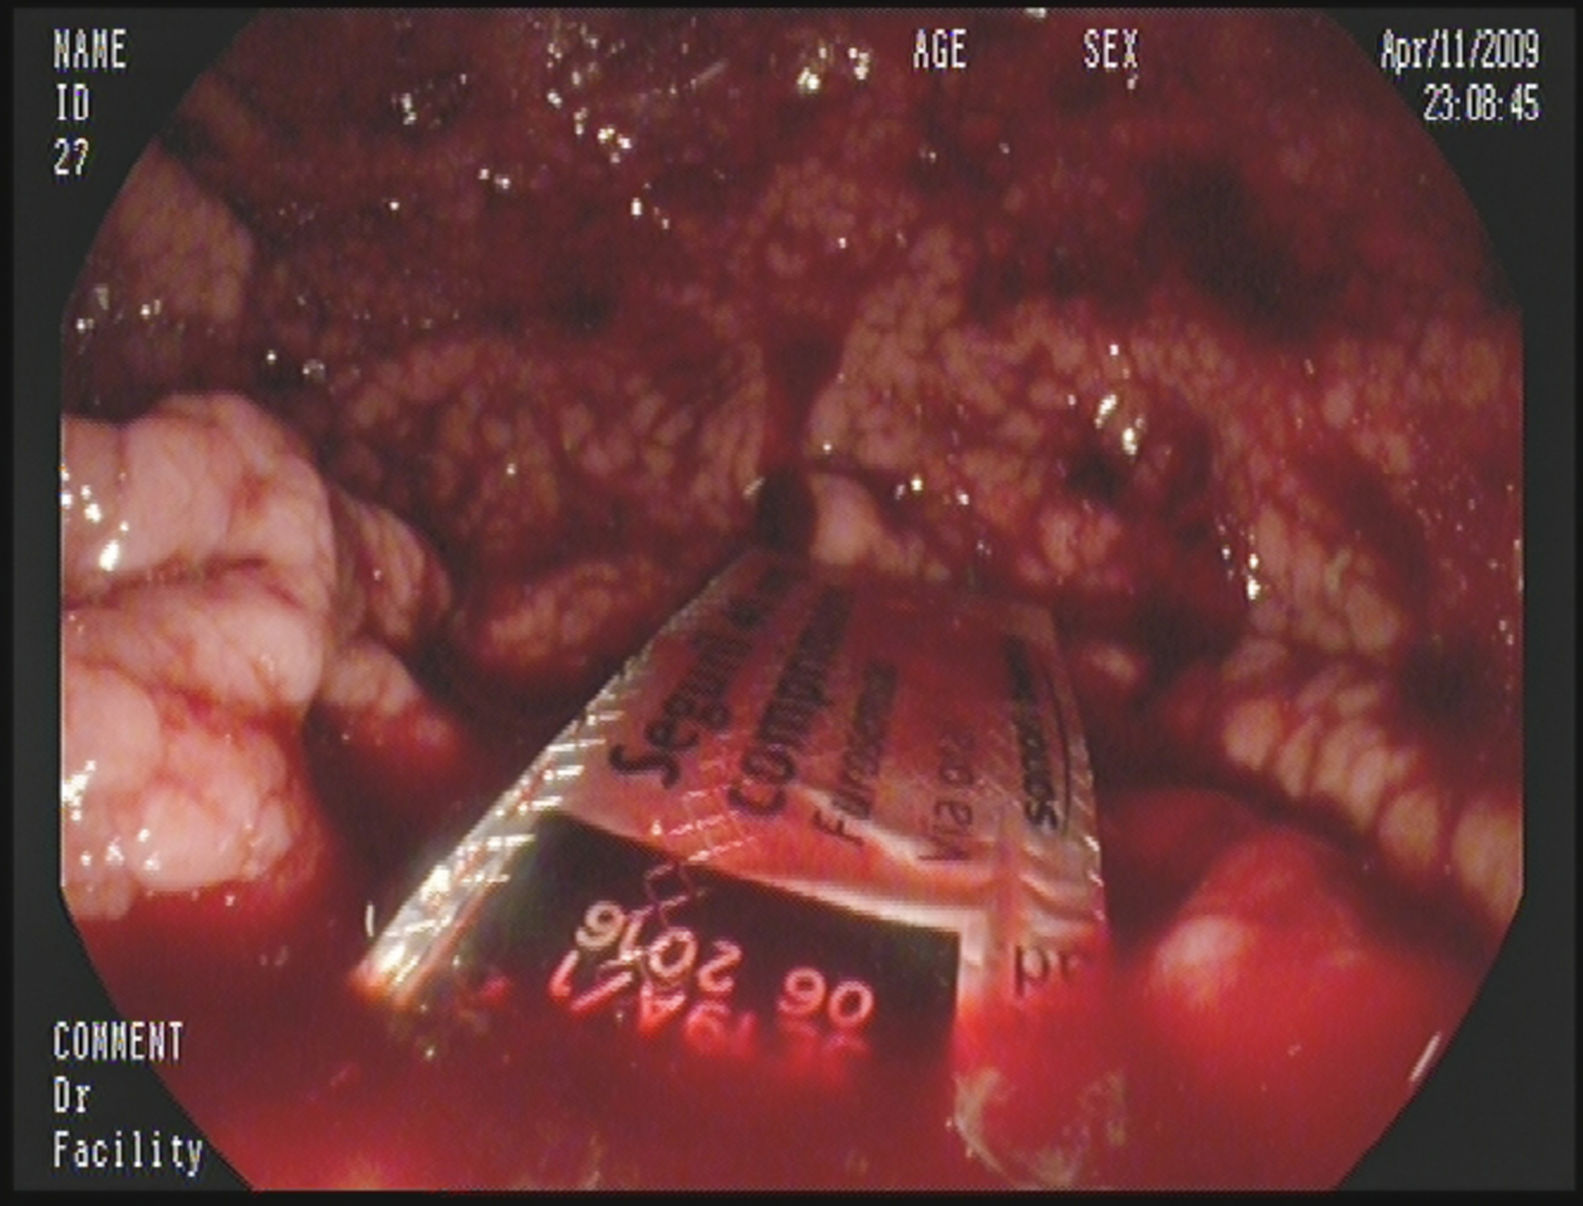

En el ámbito médico, los restos hemáticos permiten realizar pruebas que pueden revelar patologías severas, como leucemias o trastornos de coagulación. En el contexto forense, la identificación de restos hemáticos puede proporcionar información sobre las circunstancias de un crimen, como la localización de una víctima o la reconstrucción de eventos en un caso judicial. Recientemente, métodos como la espectrometría de masas han facilitado un análisis más exhaustivo y exacto de los componentes de la sangre, lo que se traduce en resultados más fiables al momento de interpretar los hallazgos.